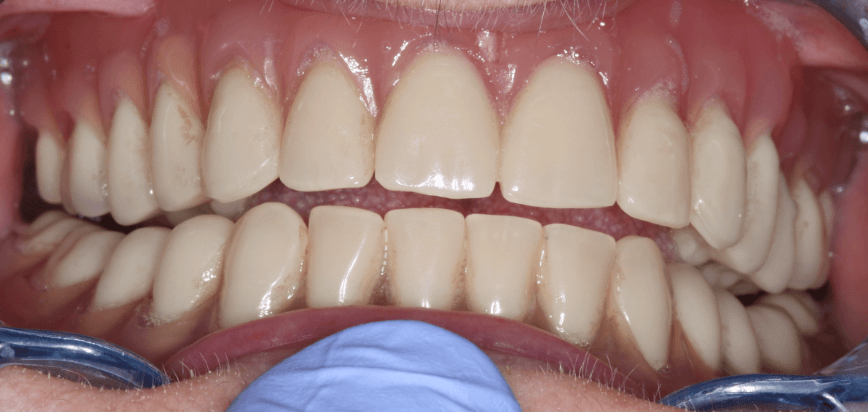

Koronák fajtái az Unikliniknél

Többféle korona is elérhető klinikánkon, a fogpótlás jellegének és a páciens igényeinek megfelelően. A hagyományosnak mondható fémkerámia-korona és cirkonkorona mellett speciális, PROCERA-technológiával készülő koronával is a pácienseink rendelkezésére állunk.

- Porcelán leplezésű kobalt-króm korona vagy hídtag (2 év garanciával)

- PROCERA korona és híd cirkónium vázra (5 év garanciával)

- Porcelán leplezésű cirkónium korona (2 év garanciával)

- Emax fémmentes préskerámia korona

- Aranykerámia korona

Milyen a jó fogkorona? Melyik a legjobb fogkorona? A válasz minden páciens, minden fogsor esetében más és más. A fenti linkeken bővebb leírást olvashat az egyes koronák jellemzőiről, és az árakról is tájékozódhat. Az ideális megoldás kiválasztásához pedig konzultáljon valamelyik fogorvosunkkal!